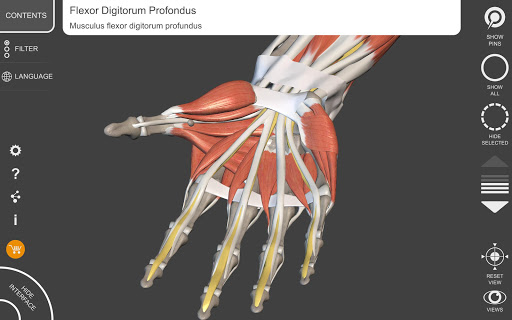

يتيح لك "Anatomy 3D Atlas" دراسة التشريح البشري بطريقة سهلة وتفاعلية.

من خلال واجهة بسيطة وبديهية، من الممكن ملاحظة كل بنية تشريحية من أي زاوية.

تتميز النماذج التشريحية ثلاثية الأبعاد بتفاصيل خاصة ودقة تصل إلى 4K.

نماذج تشريحية ثلاثية الأبعاد

• الجهاز العضلي الهيكلي

• تصور العضلات من خلال مستويات الطبقات من الطبقات السطحية إلى الأعمق

• من خلال تحديد نموذج أو دبوس، يظهر المصطلح التشريحي ذي الصلة

• وصف العضلات: الأصل والإدخال والتعصيب والعمل